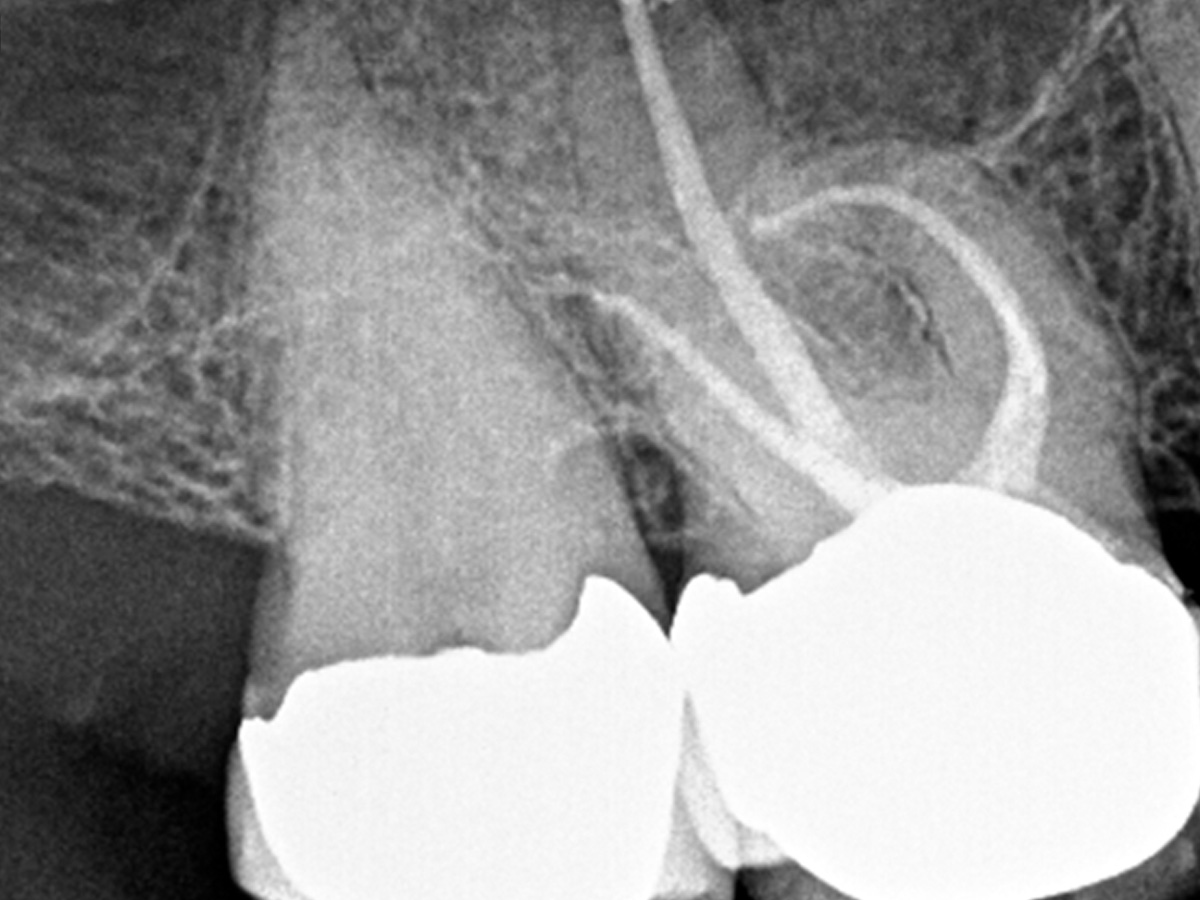

Gekrümmte Kanäle: Sicher Aufbereiten bei 1.000 RPM

In diesem Fallbericht von Zahnarzt Eduardo Belandria wird die Wurzelkanalaufbereitung gekrümmter Kanäle mit wärmebehandelten Niti-Feilen der neuesten Generation (FKG RACE EVO) bei 1.000 rmp/1,5 N-cm gezeigt.